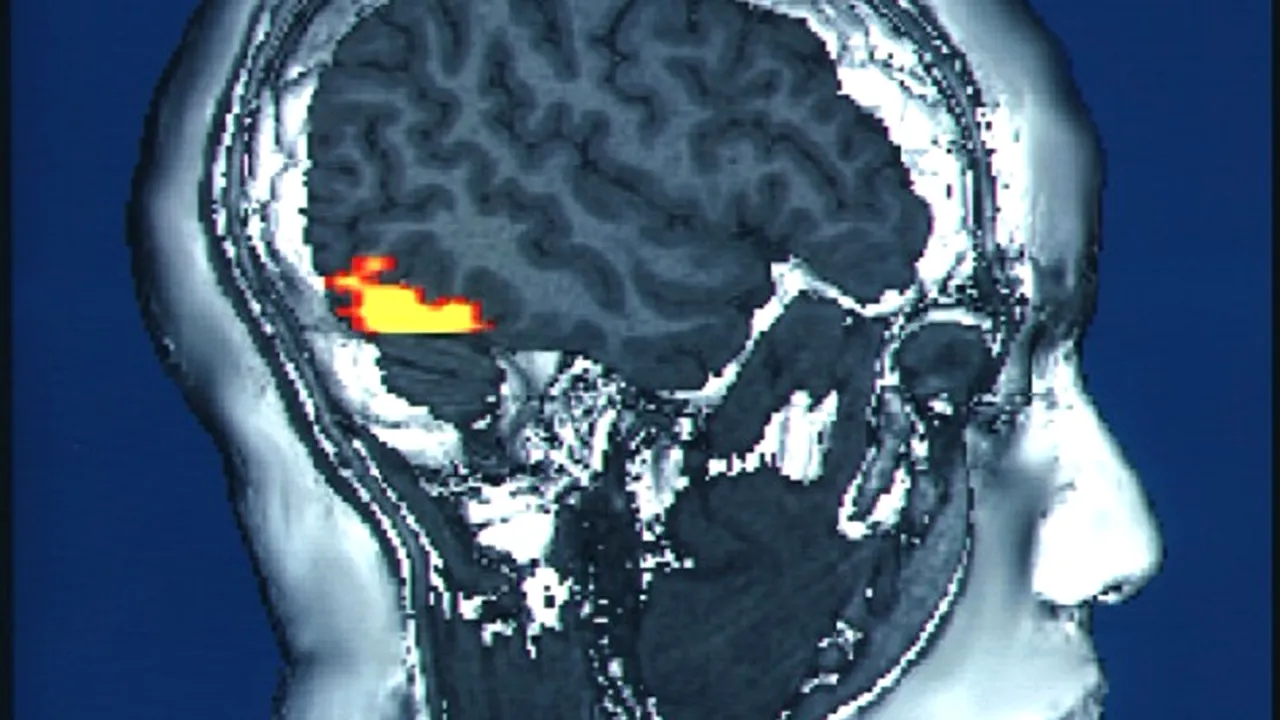

Un principiu primordial al neuroștiinței a fost demontat, după ce studiile recente au arătat că există o parte a creierului nostru care continuă să crească după ce depășim vârsta adolescenței, când se credea că creierul încetează să mai evolueze din punctul de vedere al mărimii. Este vorba despre zona creierului responsabilă cu recunoașterea de către noi a chipurilor celor din jur.

Totuși, o serie de studii recente arată un scenariu contrar acestui crez. Oamenii de știință au studiat acea parte a creierului care este responsabilă cu recunoașterea fețelor, zona fusiformă, dezvoltată doar în cazul ființelor umane și al maimuțelor mari.

În cadrul cercetării au fost comparate creierele copiilor cu vârste cuprinse între 5 și 12 ani și cele ale adulților între 22 și 28 ani, folosindu-se de două rezultate obținute cu ajutorul analizei de tip RMN. Una dintre analize indicat fluxul sanguin, în timp ce cealaltă arăta raportul dintre cantitatea de țesut și cea de apă.

Cercetătorii au observat că țesutul continuă să se dezvolte în zona fusiformă în cazul adulților. Acest lucru înseamnă o îmbunătățire a capacității noastre de recunoaștere a fețelor odată cu înaintarea în vârstă, deși foarte multe persoane consideră că țesutul cranian resposanbil cu această abilitate dispare încetul cu încetul de îndată ce începem să îmbătrânim.

Dincolo de legătura între dezvoltarea continuă a creierului și îmbunătățirea capacității de recunoaștere a fețelor, acest studiu ar putea conduce la găsirea unor explicații pentru care 2% din populația adultă a lumii nu poate recunoaște fețe. Această disfuncție este cunoscută sub numele de prosopagnozie.